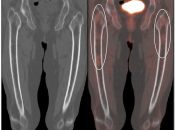

Normal Skeletal Uptake

Mild to moderate FDG uptake can be normally seen within red marrow, most commonly affecting the vertebral bodies, sternum, pelvis, and proximal long bones (it is not unusual to see fairly prominent uptake within the proximal half of the femurs). This red marrow uptake can be quite heterogeneous at times, yet still normal.

Diffuse Skeletal Uptake:

Intense and diffuse reactive marrow uptake is frequently seen as the result of chemotherapy and/or colony stimulating factors (discussed in detail, here).

If rather diffuse and intense uptake is noted without a history of recent chemotherapy or colony stimulating factors, be suspicious of infiltrating disease such as lymphoma.

Focal Skeletal Uptake:

Focal skeletal uptake warrants extremely close assessment of the co-registered CT images to exclude malignancy. Other etiologies of focal skeletal uptake include fracture, arthropathy, infection and several benign bone lesions.